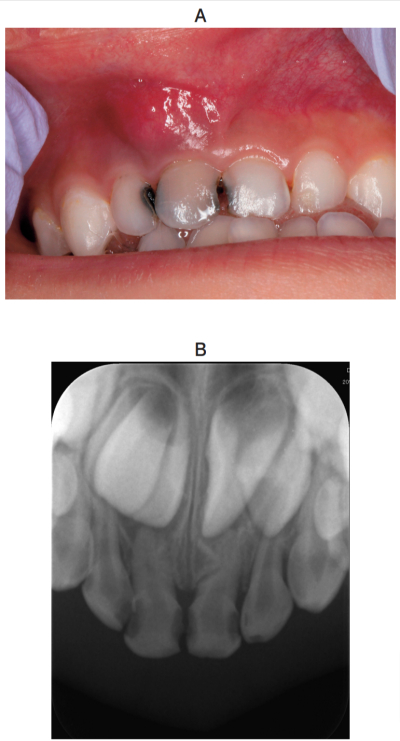

5歳の男児。上顎右側乳中切歯の歯肉腫脹を主訴として来院した。3日前から腫脹し咬合時に痛みがあるという。初診時の口腔内写真とエックス線写真を別に示す。

適切な対応はどれか。1つ選べ。